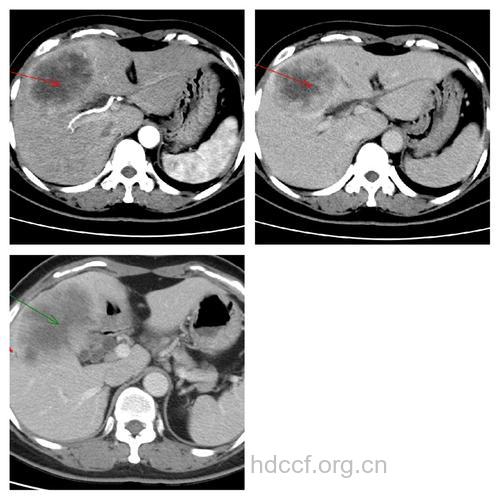

CT的出现使肝癌影像学诊断有了一个质的飞跃,并带动了肝脏外科的进步。CT的分辩率远远高于超声,图像更加清晰和稳定,更能全面客观地反映肝癌的特性。CT检查可清楚地显示肝癌的大小、数目、形态、部位、边界、肿瘤血供丰富程度,以及与肝内管道的关系;对门静脉、肝静脉和下腔静脉是否有癌栓,肝门和腹腔淋巴结是否有转移,肝癌是否侵犯邻近组织器官都有很重要的诊断价值;CT还可通过显示肝脏的外形、脾脏的大小以及有无腹水来判断肝硬化的轻重。快速螺旋CT能在一次屏气(20s左右)即可完成整个肝脏的扫描,可避免呼吸运动所致层面的上下移动而漏扫微小病灶,还可克服呼吸运动产生的伪影问题。螺旋CT最小可用1mm的层厚进行薄层扫描,对1~3cm的小肝癌检出率可达90%,并能在螺旋扫描的长度内实施高质量的三维图像重建。对增强CT难以作出明确诊断的肝癌,还可进一步采用血管造影CT。经皮导管在肝动脉注入造影剂,观察肝动脉显影时的CT,称CT血管造影。